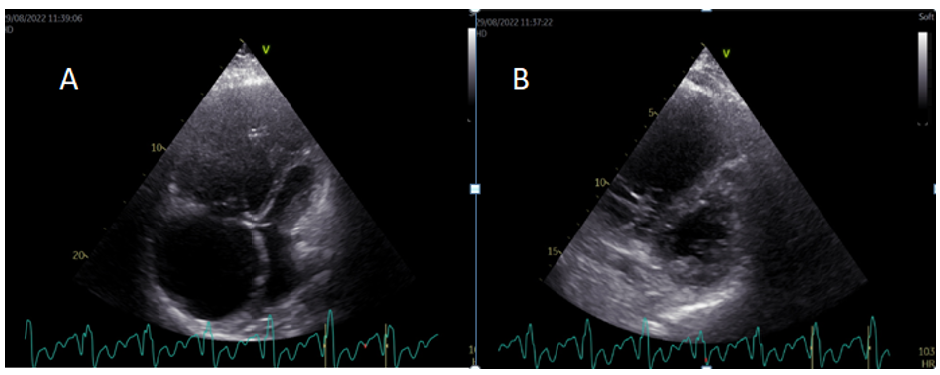

Chronic Thromboembolic Pulmonary Hypertension Presented as Acute Heart Failure: A Case Report

Elizabeta Srbinovska Kostovska, Lazarova E, Kostovski L, Bosevski M, Kjaeva-Anastasova S and Pejkov H. 6(5): 37-42.